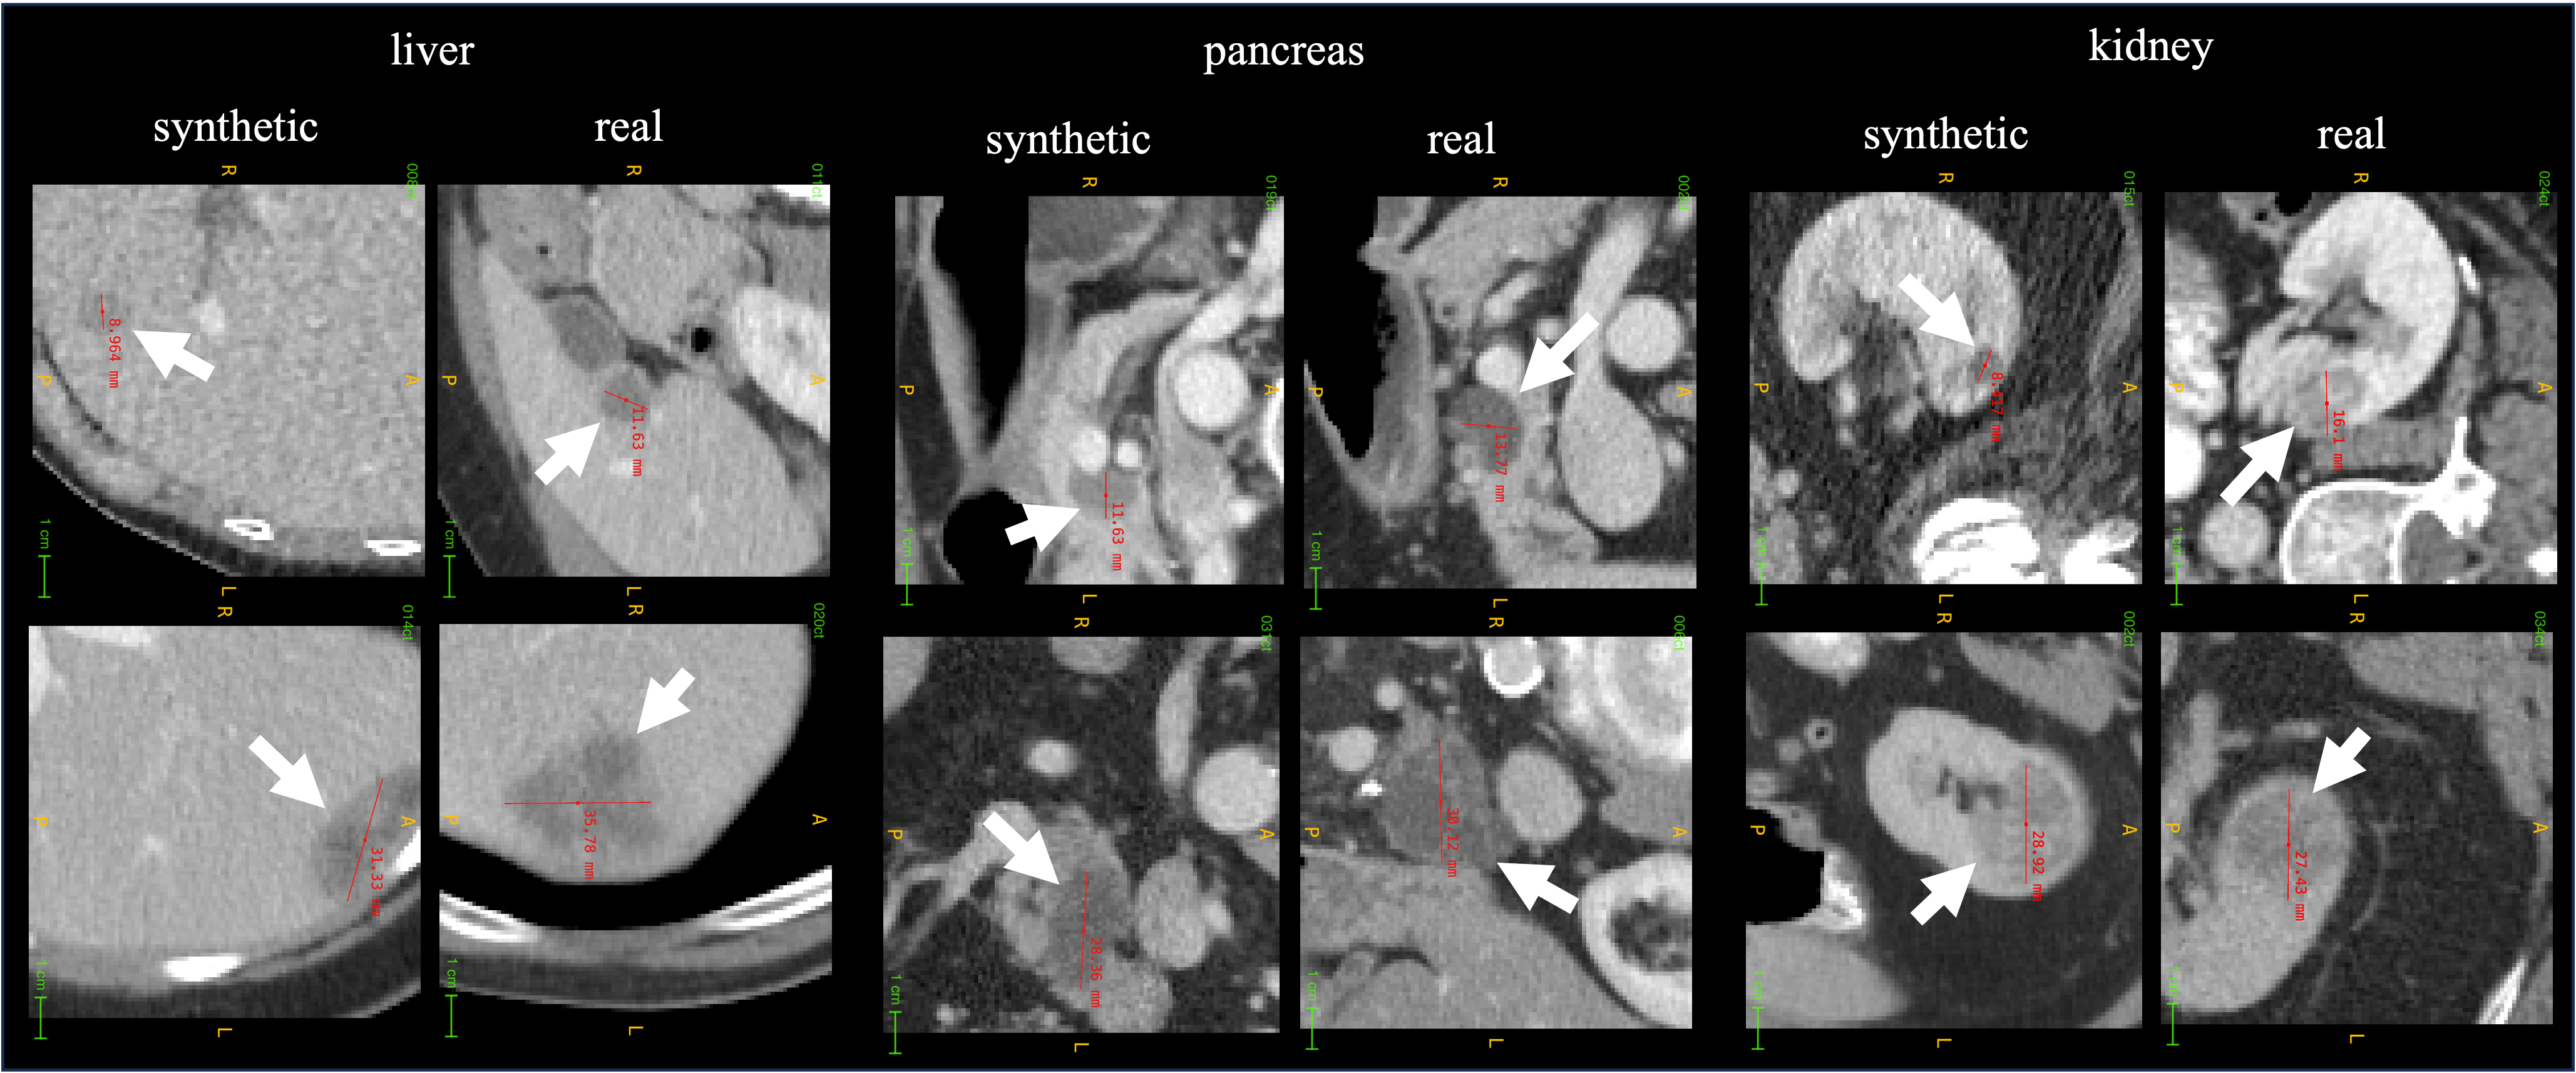

Figure 5: Synthetic liver, pancreatic, and kidney tumors generated by Cellular Automata lai2024pixel .

Refer to caption

Figure 6: ① Tumor development: The cellular automata simulate tumor growth from a single pixel to various sizes and even tumor death, producing synthetic tumors with diverse sizes, shapes, and textures. An idealized tumor is created to quantify development, with dead cells in the gray region, living quiescent cells in the inactive region, and proliferative cells in the active outer shell. ② Tissue quantification: The organ map in blue transforms CT images into distinct intensity levels affecting tumor development rate, while the red tumor map assigns values representing the tumor cell population. ③ Tumor interaction with boundaries and vessels: The tumor grows and exerts pressure against organ boundaries and deforms as it interacts with vessels. ④ Mapping synthetic tumors to CT images: A mapping function correlates the synthetic tumor with CT values, integrating the tumor’s state with the original CT intensity. ⑤ Training segmentation models with synthetic data: Pixel2Cancer generates new synthetic data for each epoch to train the segmentation model.

Cellular Automata are computational models used to simulate complex systems through simple rules and interactions. They employ a grid of cells (pixels), where each cell is initially assigned a state between zero and ten to represent the tumor population. The basic element is the cell, which refers to a single pixel in the computed tomography (CT) image. Tumor growth and behavior are modeled based on specific rules that simulate processes such as proliferation, invasion, and death. These rules are derived from medical knowledge and are guided by an idealized tumor model that reflects real-world characteristics. The tumor state can then be integrated into the original CT images to generate synthetic tumors in different organs. This tumor synthesis approach allows for sampling tumors at various stages and analyzing tumor-organ interactions. Motivated by this, Lai et al. lai2024pixel proposed Pixel2Cancer to simulate tumor growth (Fig. 6). Tumors generated by Pixel2Cancer are illustrated in Fig. 5.